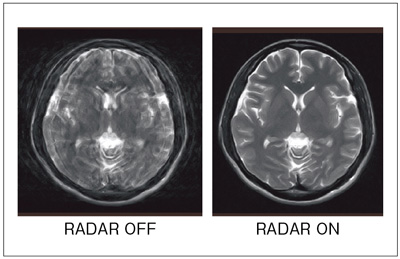

モーションアーチファクトを低減する計測法である“RADAR*”は,計測時のデータ取得方法を工夫することで効果的にアーチファクトを分散,低減します。図4にRADARの頭部への適用例を示します。Resolution modeとTime modeの選択が可能で,従来の計測と同等の空間分解能,または撮像時間を選択できます。日立のRADARは適用シーケンスや適用部位の自由度が高い点が特長です。(*オプション)

図4 RADARによるアーチファクト低減効果